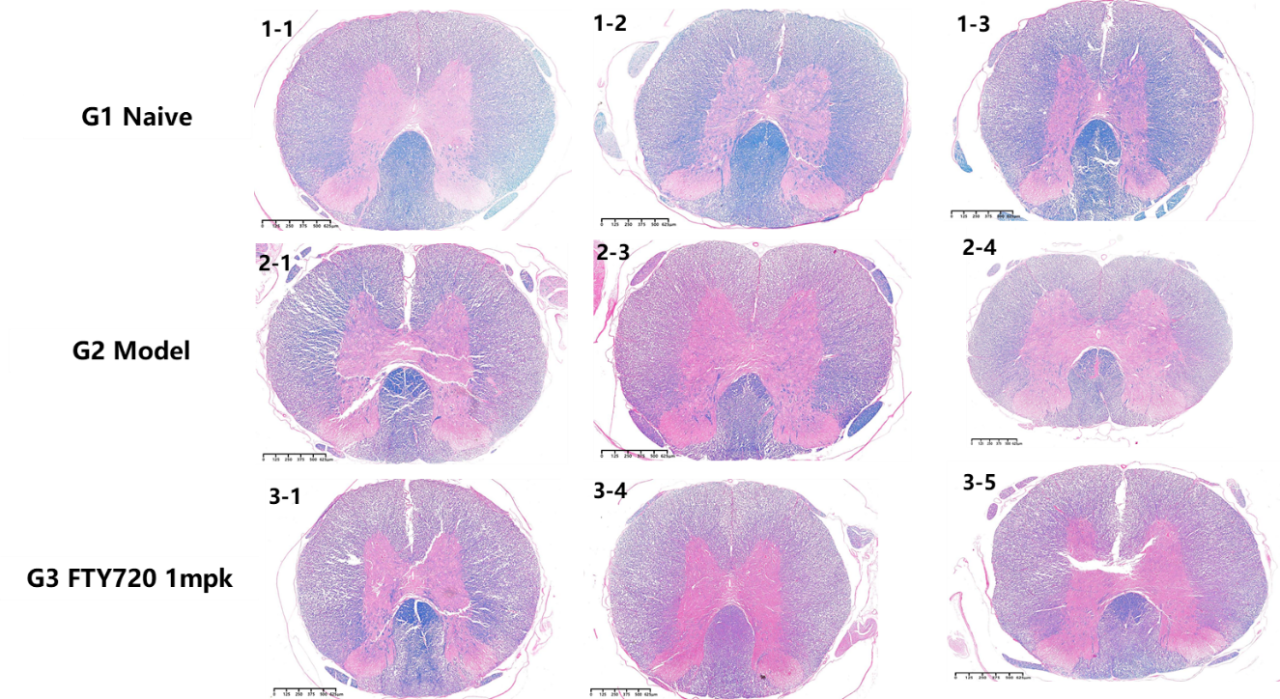

腦組織H&E染色

腦組織HE結(jié)果顯示,模型組炎癥評(píng)分顯著高于空白對(duì)照組,芬戈莫德可以顯著降低脊髓炎癥反應(yīng)。

圖6 腦組織H&E染色代表圖像

圖7 腦組織炎癥評(píng)分